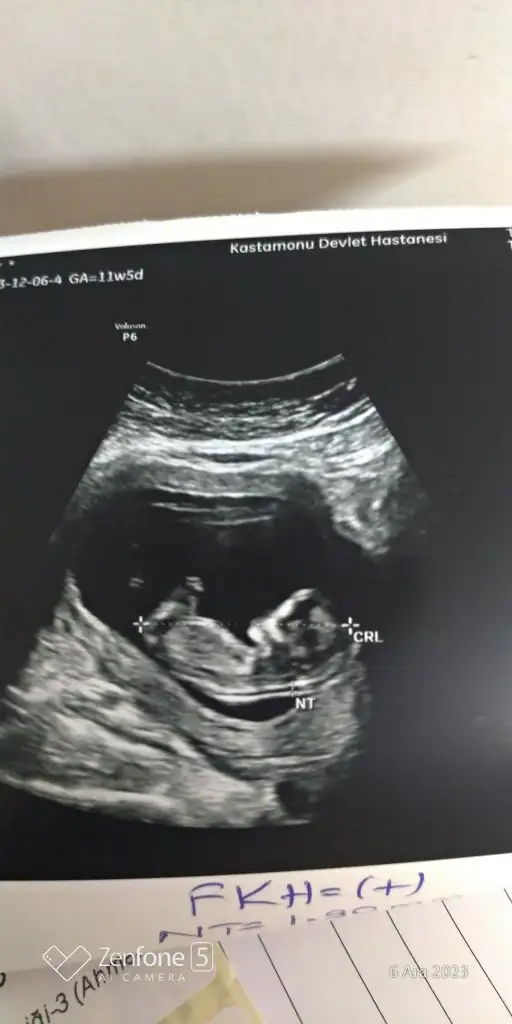

Nub teoriye göre bakarmisniz?